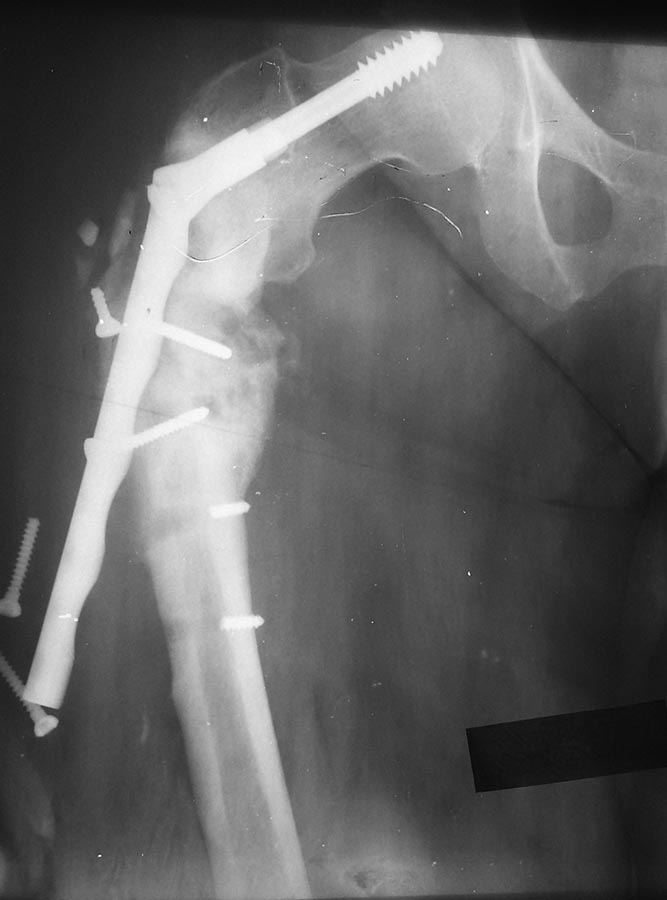

Больная 39 лет. Полная. В анамнезе тяжёлая ЧМТ с левосторонним

гемипарезом и дисфазией.

Больная впервые оперирована мной 2.5 года назад. Имел место оскольчатый

подвертельный перелом. Поставил подвертельную пластину Double medical.

Но поскольку у больной имеет место левосторонний гемипарез и дисфазия

после перенесённой ЧМТ, она стала сразу ходить с полной нагрузкой. В

итоге через полгода перелом метфиксатора. При повторной операции был

установлен DHS на длинной ножке. Спустя год смотрел снимки - выраженная

костная мозоль. И вот вчера после предварительного падения, я снова с

ней встретился. По сегодняшним результатам СКТ перелом свежий. Я

предлагаю удадение DHS, установку PFN с возможной костной пластикой.

Коллеги, что посоветуете?